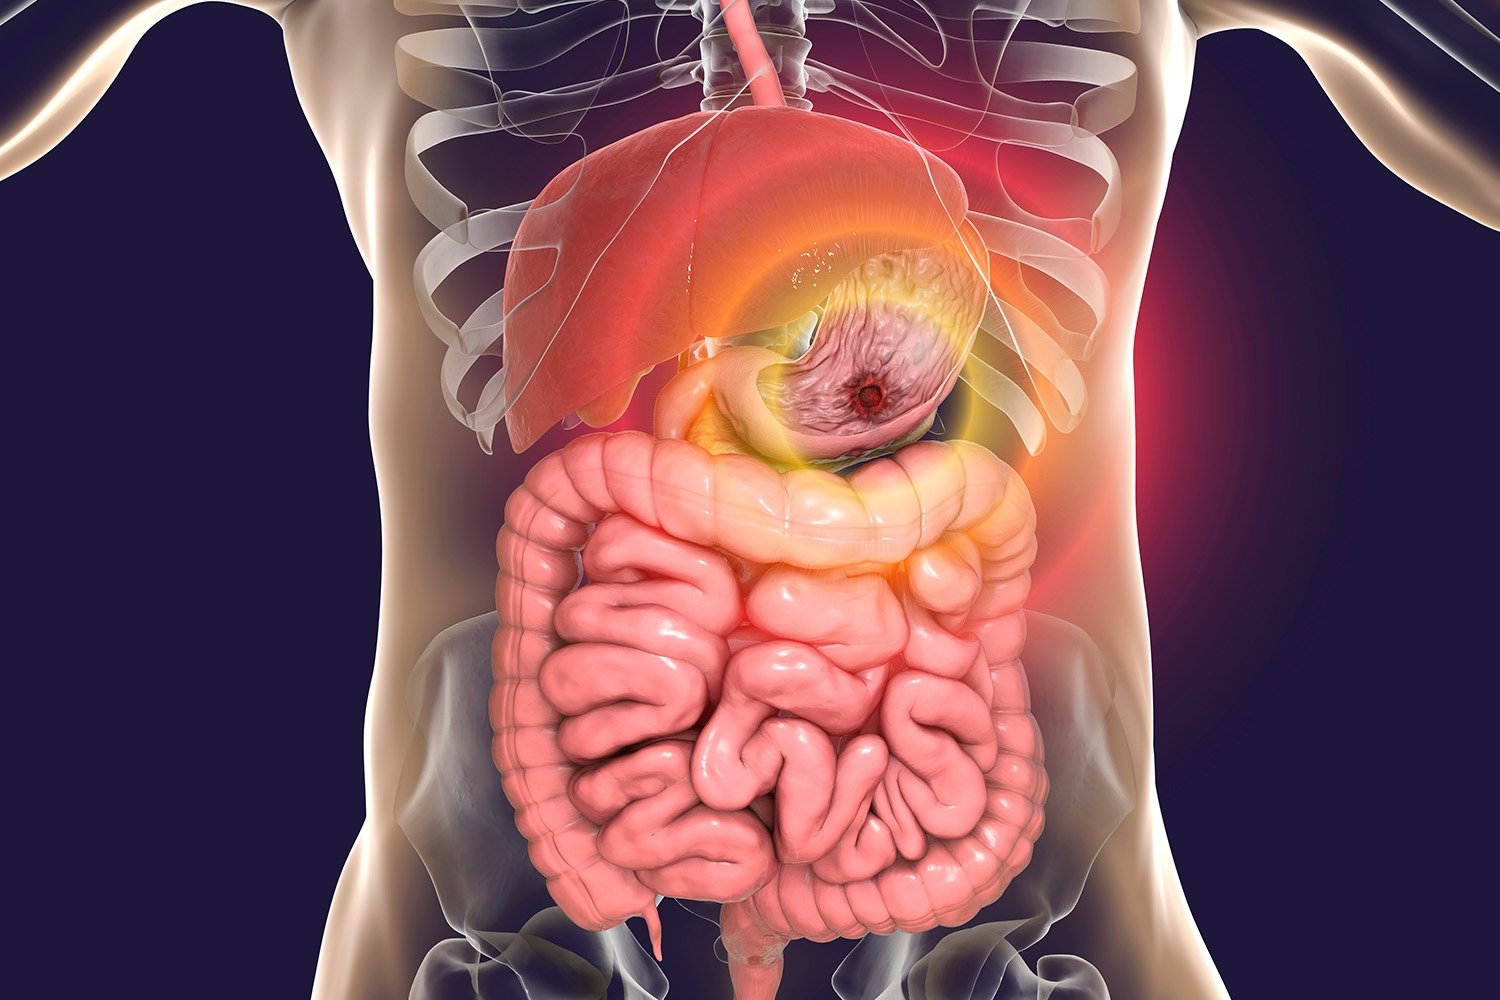

Gastroenterology

Medicon Clinical Lab offers a broad range of gastrointestinal tests to identify digestive disorders and related infections. Using advanced diagnostic technologies, we assist physicians in detecting conditions like celiac disease, liver dysfunction, and gut inflammation — enabling early diagnosis and effective patient care.

Oncology

Our oncology testing services help in the early detection, diagnosis, and monitoring of various cancers. Through biomarker and tumor marker analyses, we provide valuable data that guides physicians in developing effective treatment plans and tracking therapy progress for improved patient outcomes.